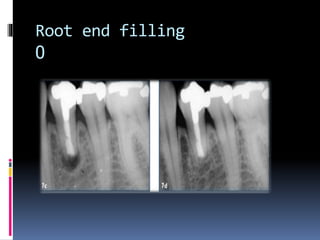

Root end filling

0